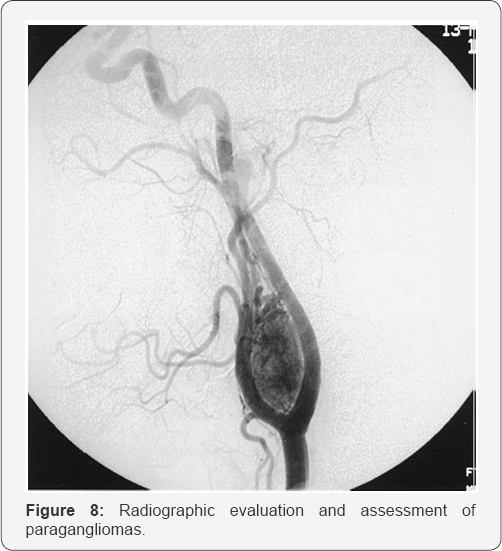

DSA: Digital subtraction angiography

Demonstrates the primary arterial supply and collateral vessels of tumor

a. Reveals relationships with neck blood vessels

b. Angiography is also helpful for better visualization of the feeder vessels and is of utmost importance for high-risk tumors (Shamblin II or III) that need either embolization or a preoperative balloon occlusion test (Figure 8).